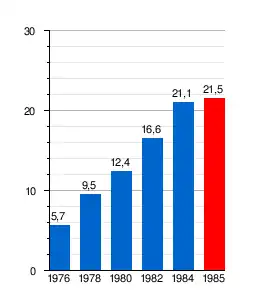

Desde principios de la década de 1970 y hasta mediados de la década de 1980 su consumo experimentó un verdadero boom mundial –solo en Europa el número de adictos se quintuplicó entre 1967 y 1977–[29] que se dejó sentir hasta bien entrada la década de 1990 y que provocó la muerte de miles de personas, fundamentalmente jóvenes de países occidentales; en países de Europa como Alemania, España, Francia o Italia el fenómeno resultó en una verdadera epidemia, donde tuvo especial incidencia en las clases bajas de la población.[29]

En Alemania Occidental (RFA) la epidemia fue descrita como la más grave de toda Europa, al menos en la década de 1970;[30] según estimaciones federales, en 1978 había 60.000 heroinómanos,[30] en la RFA se incautaba la mitad de la heroína de toda Europa y más de 700 personas morían por sobredosis cada año.[30] Estos hechos fueron retratados en la simbólica novela, que se convirtió en lectura obligada en las escuelas, llamada Los niños de la estación del Zoo y que fue llevada al cine con el nombre de Yo, cristina F. y que contó con la participación de David Bowie, quien admitió ser consumidor de esta sustancia.

En el caso de España su uso no empezó a generalizarse hasta después de 1975, tras la muerte de Francisco Franco y el comienzo de la Transición a la democracia, donde se vivía una atmósfera y anhelo de absoluta libertad donde prevalecía el «todo vale» tras la férrea dictadura. Unido a ello se produjo, sobre todo desde comienzos de la década de 1980, una fuerte reconversión industrial, que disparó el desempleo en las antiguas regiones industriales como Madrid, Cataluña y en especial el País Vasco, cuya economía dependía de la industria pesada, principal objetivo de la reconversión, que acabó prácticamente con todo el sector sin ofrecer alternativas.[31] En estas regiones fue precisamente donde la epidemia de heroína más se cebó con la población;[32] en 1979 se estimaba que en Barcelona había 30 000 heroinómanos, un 1% de la población[33] y algunas estimaciones apuntaban a que en toda España su número podía rondar los 80.000 en 1984, concentrados la mayoría en Barcelona, Madrid (6000 jóvenes consumidores habituales)[34] y el País Vasco.[32] Solo entre 1982 y 1984, las muertes de adictos se duplicaron.[34] En 1984 algunas estimaciones cifraban en 117.000 millones de pesetas (unos 700 millones de EUR) el dinero que este mercado movía al año.[32] En España la epidemia afectó a toda la sociedad y en las regiones más afectadas el tráfico y consumo de drogas estuvo entre las principales preocupaciones de la población hasta bien entrada la década de 1990. Su incidencia se dejó sentir en la criminalidad, que aumentó considerablemente y alcanzó sus máximos durante la epidemia; en 1985, el Ministerio del Interior estimaba que el 75% de los delitos comunes estaban asociados al tráfico o consumo de drogas,[34] al respecto, el número de detenidos por tráfico o tenencia de drogas, que en 1970 fue de 1200,[33] había aumentado hasta los 5200 en 1977[33] y escalado hasta unos 11 000 en 1984.[35] Otro dato revelador eran los atracos a farmacias, que en 1977 fueron 718 solo en Madrid, cuando en toda Francia fueron 750 y 1500 en la RFA.[33] Dicho masivo consumo duró hasta la primera mitad de la década de 1990 (a menudo se toma la referencia de 1992). Las películas de cine quinqui como El pico retratan a la perfección esta epidemia que se cebó en barrios obreros masificados y en los que la juventud no tenía ningún futuro por la crisis económica, y donde muchos de los protagonistas de estas películas murieron por su adicción a esta droga.

El consumo continuó creciendo hasta mediados de la década de 1980,[35] cuando se estancó y comenzó a descender fuertemente,[39] sus motivos fueron varios. Las enfermedades de transmisión sexual (ETS) hacían estragos entre los consumidores, especialmente con la aparición del sida en los años 80, que entonces era una enfermedad muy dura e incurable y que se transmitía cuando los consumidores compartían las jeringuillas, lo que provocó que muchos jóvenes no se atrevieran a probar esta droga. Lo mismo sucedió con el miedo a contagiarse de otras enfermedades como la hepatitis. Paralelo al descenso de heroína se produjo el ascenso del consumo de cocaína en Europa y los Estados Unidos,[39] que se convirtió en la droga de referencia. La cocaína se puso de moda entre famosos y las clases altas (como ejecutivos),[35] y la sociedad acabó imitando el comportamiento de estas «élites». En Estados Unidos unas 22 millones de personas consumían cocaína en 1985 (casi un 10% de su población),[39] consumo que se extendió hasta desatarse la epidemia de crack de los años 90, aunque esta afectó sobre todo a las clases bajas y minorías étnicas. De esta forma se acabó creando la imagen de la cocaína como la «droga del rico» y la heroína como la «droga del pobre»,[39] aunque el precio de la heroína siguió siendo mayor.[35] A su descenso también pudo afectar la cada vez mayor conciencia social del problema, en el que se creaban asociaciones para combatir el problema y dejar de ver al consumidor como un delincuente y verlo como un enfermo que necesitaba ayuda; la evidente imagen de degradación física y psicológica que provocaba la adicción en los drogadictos y el daño a sus seres queridos provocó un fuerte impacto en la sociedad y «demonizó» la heroína para la siguiente generación.